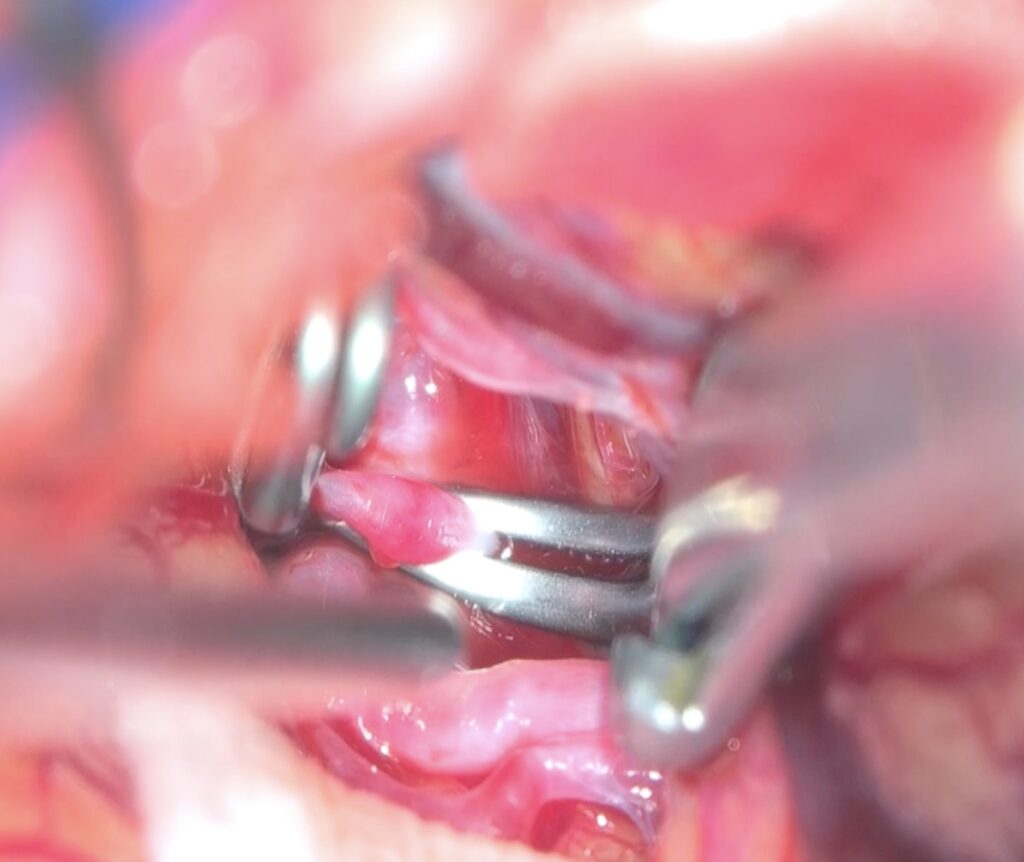

コンビネーションクリップでクリップしました。最終クリップに至るまでに、両側M2が十分流れるように書け直しを2回ほど行いました。ドームをしっかり剥離してぶらぶらにすること、クリップを一回でなくベストクリップになるまで何度もやり直すのが京大伝統の教えです。